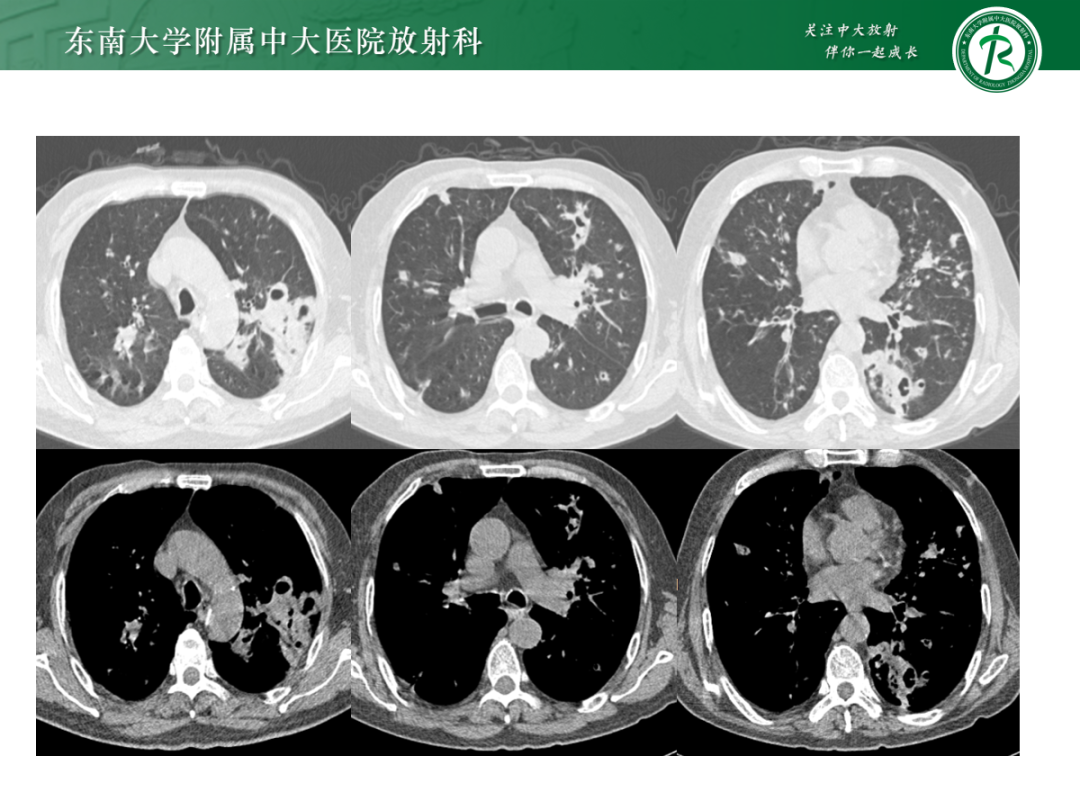

• 病例1:鸟型分枝杆菌复合体肺病

• 病例2:肺诺卡菌病

• 病例3:肺结核

• 病例4:气道侵袭性肺曲霉菌病

影像诊断思路